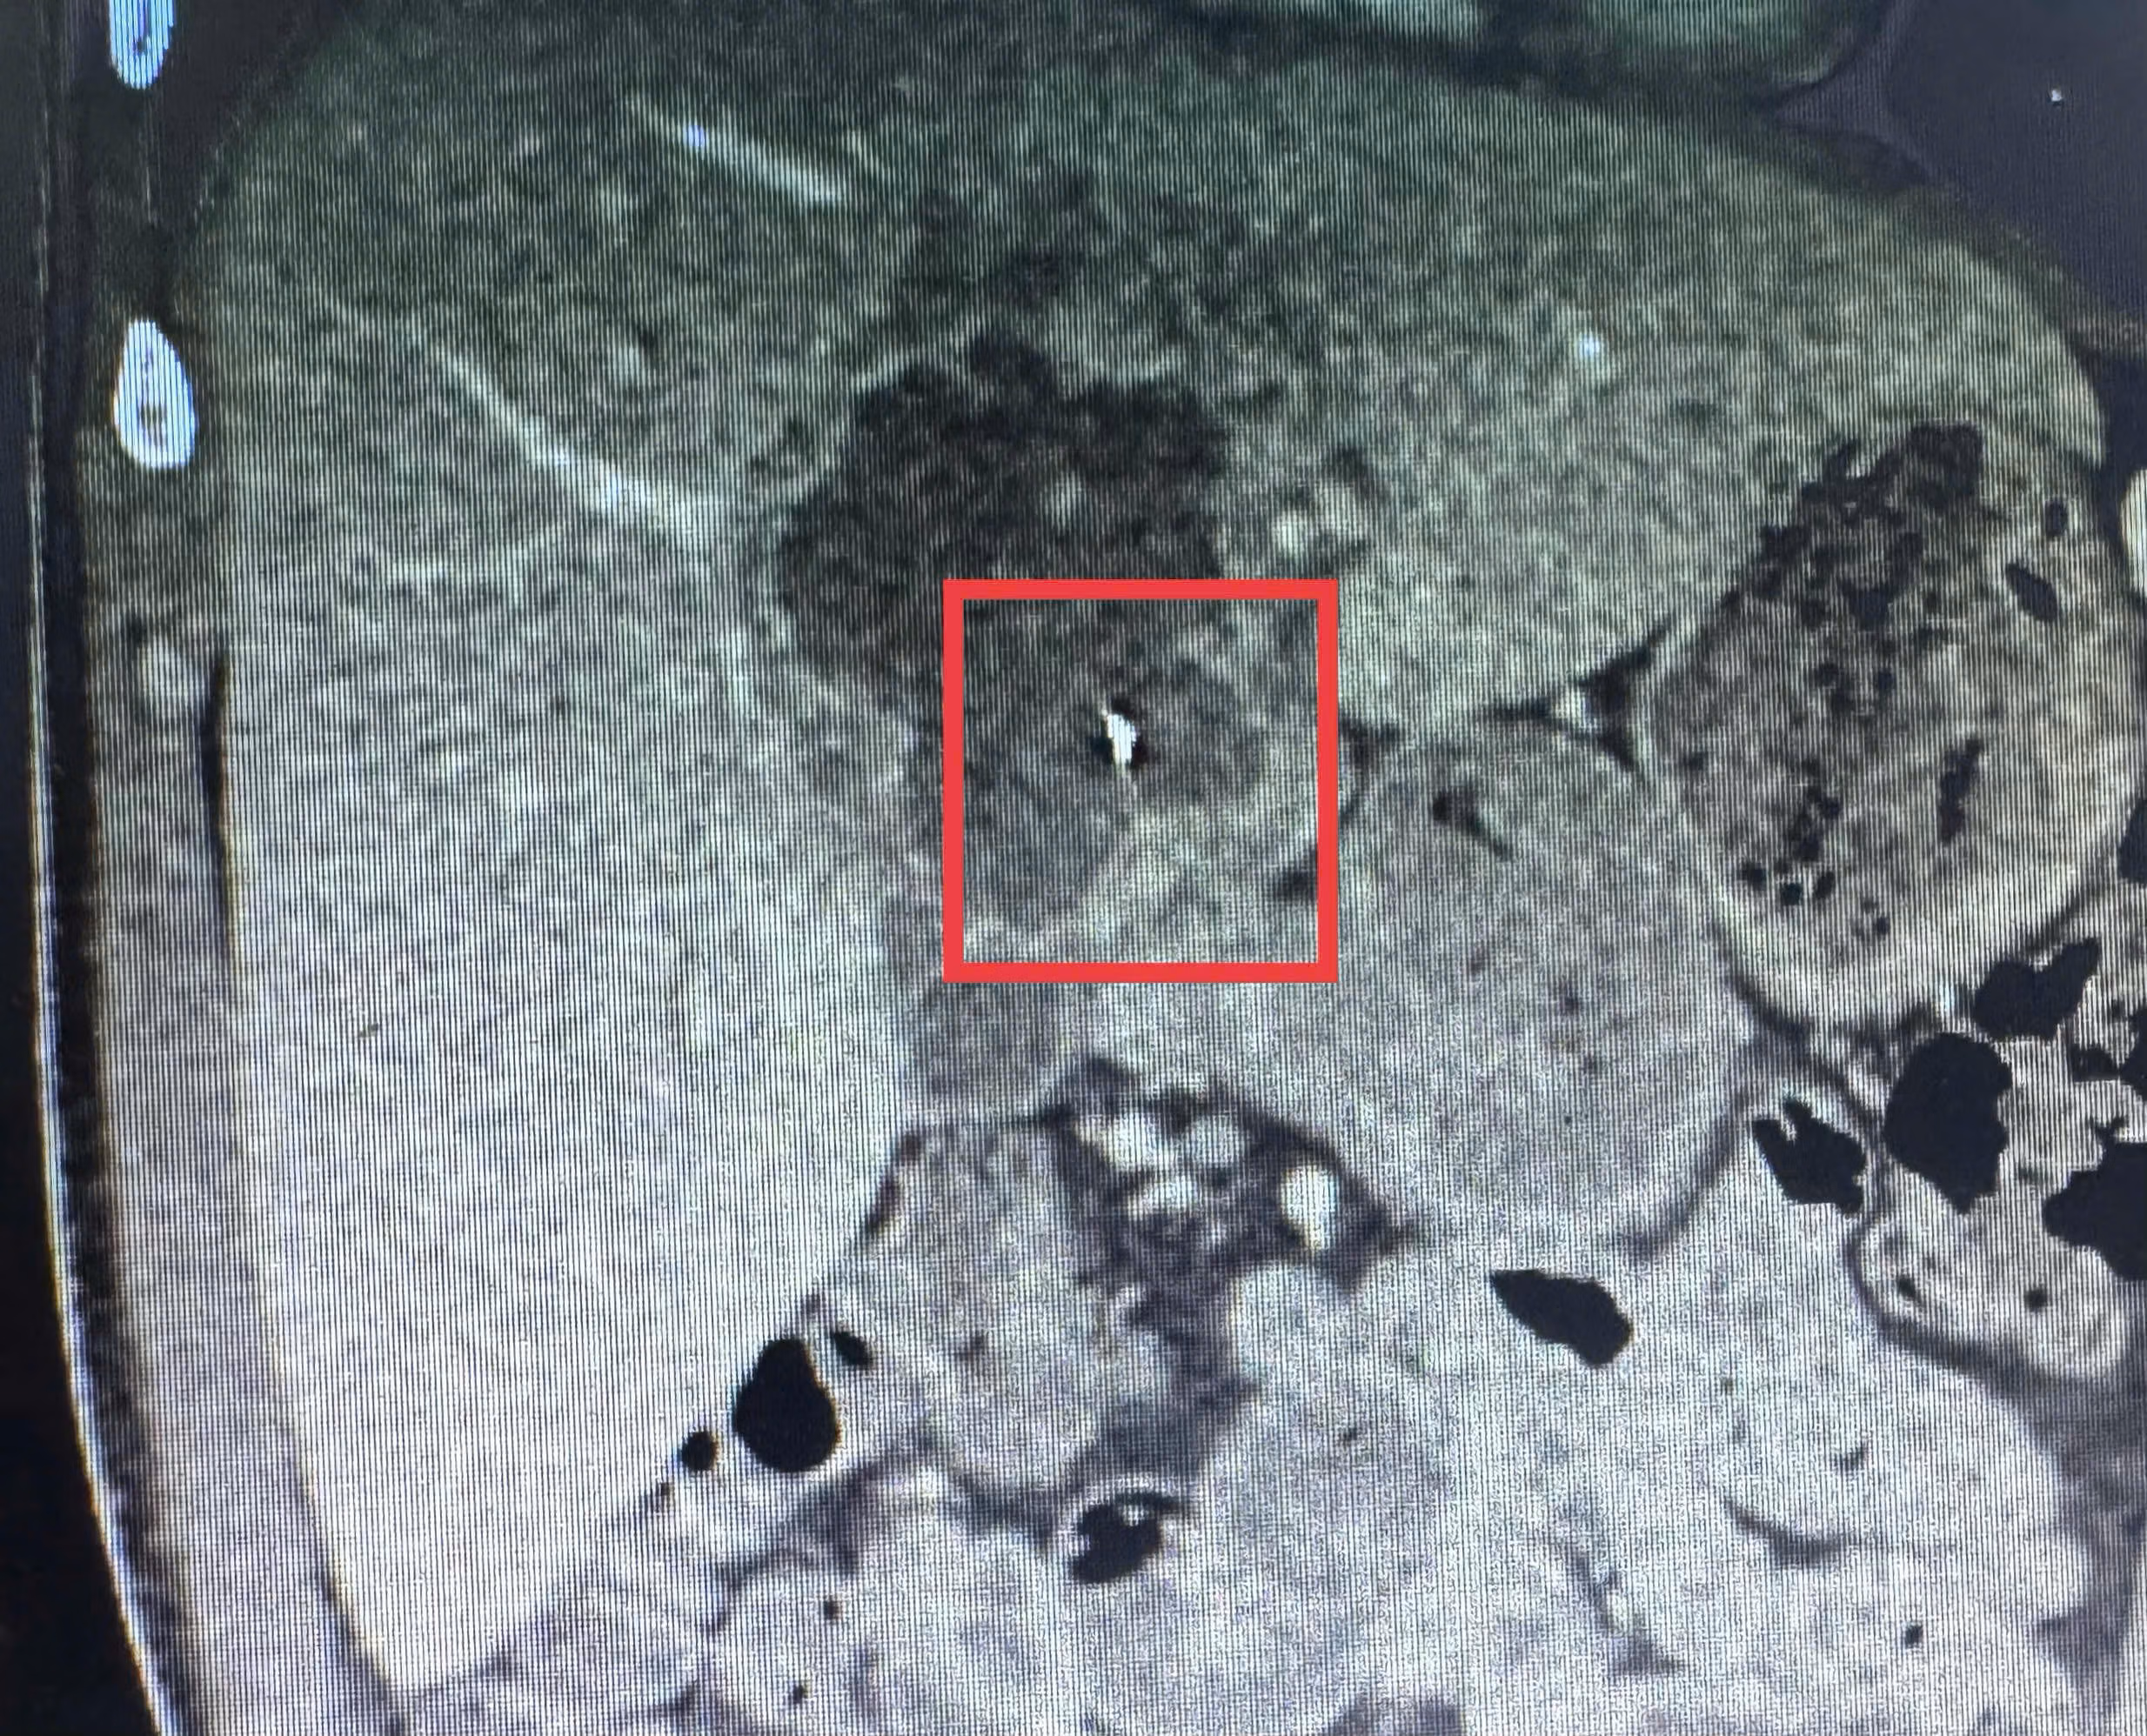

Trước đó, ngày 9/2, bệnh nhân T.T.L (41 tuổi, ngụ xã Nhơn Phú, tỉnh Vĩnh Long) nhập viện trong tình trạng đau dữ dội vùng thượng vị kèm sốt cao. Qua thăm khám lâm sàng, kết hợp siêu âm ổ bụng và chụp CT-scan, các bác sĩ phát hiện ổ áp xe gan kích thước khoảng 5x6 cm, bên trong có dị vật kim loại dài khoảng 6 cm, tình huống hiếm gặp.

Theo ThS.BS.CKI Trần Nhật Phi, khó khăn của ca bệnh là ổ áp xe nằm sâu trong nhu mô gan, dị vật ở vị trí gần các mạch máu lớn nên việc tiếp cận và xử lý đòi hỏi sự thận trọng cao để bảo đảm an toàn và xử lý triệt để ổ nhiễm trùng.